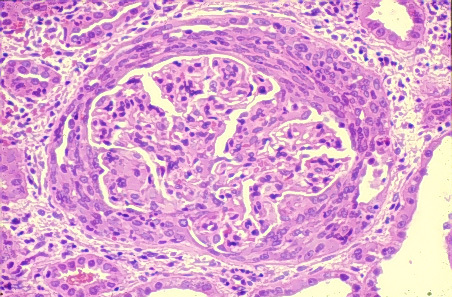

PT is a 56-year old woman with no significant medical history who presents with 2 months of LE swelling, nocturia and foamy urine

On exam, BP 138/76, periorbital edema, 3+ pitting edema of LE

Laboratory studies: Cr 1.3, TC 556, Albumin 1.8, Ur Protein: Cr ratio 13, C3 135, C4 38

HIV, HBV, HCV, ANA all negative

IgM deposition noted in histologic sample below. What is her diagnosis and treatment?

Focal segmental glomerulosclerosis:

AKA: Focal Sclerosis

Histology:

Light microscopy:

- Mesangial cell proliferation

- Focal process: not all glomeruli involved

- Segmental process: only tufts involved

- Trichrome stain: expansion of mesangium